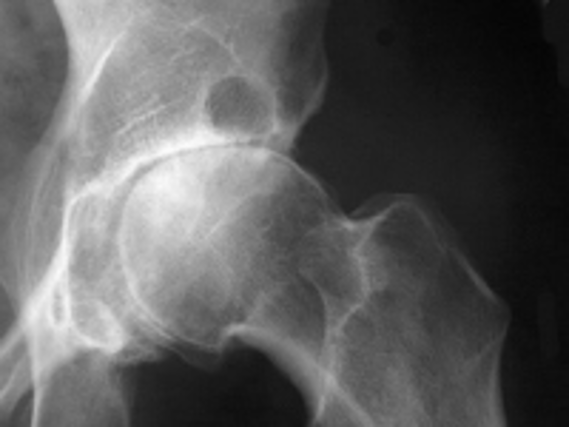

osteochondroma (exostosis)

benign projection of bone w/ a cartilaginous cap

idiopathic, hereditary

what is the cause of osteochondroma?

pt w/ osteochondroma

what is this image?